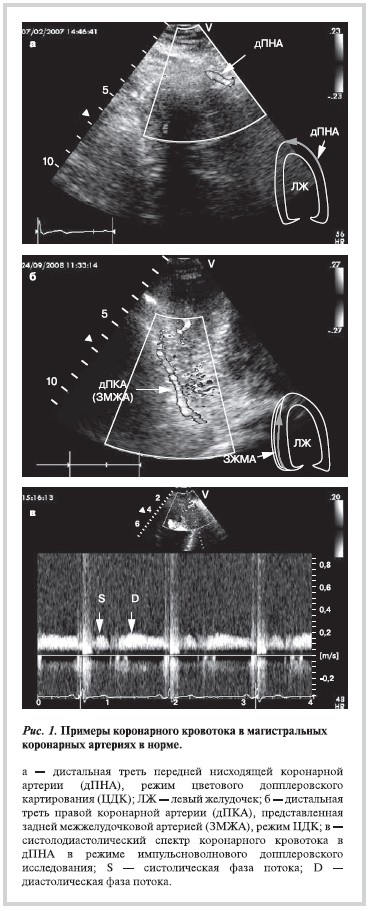

Поиск дистальных сегментов ПНА и ПКА осуществляли из апикального доступа в модифицированной 2-, 3- или 5-камерной позиции в режиме цветового допплеровского картирования (ЦДК), предел Найквиста составлял 12—20 см/с [36, 37]. Дистальную треть ПНА визуализировали в модифицированной 2- или 5-камерной позиции в передней межжелудочковой борозде дистальнее передней латеральной папиллярной мышцы (рис. 1, а). В норме кровоток в дистальной трети ПНА в данной позиции был направлен от основания к верхушке сердца, сосуд в режиме ЦДК был окрашен в красный цвет. Дистальной третью ПКА у всех пациентов условно считали ЗМЖА, которую визуализировали в задней межжелудочковой борозде в апикальной 2- или 3-камерной позиции (рис. 1, б). Иногда для лучшей визуализации ЗМЖА требовалась ангуляция датчика в каудальном направлении. Направление кровотока в ЗМЖВ в данной позиции было аналогично направлению кровотока в дистальной трети ПНА. Добивались такой визуализации ПНА и ЗМЖА, чтобы угол между направлением хода сосуда и направлением ультразвукового луча не превышал 30°.

Допплеровский спектр коронарного кровотока. После получения устойчивого изображения фрагмента сосудов длиной не менее 1 см на протяжении всего кардиоцикла, используя импульсноволновой допплеровский режим, регистрировали систолодиастолический спектр коронарного кровотока в ПНА и ЗМЖА (рис. 1, в). Ширина контрольного объема составляла 2—3 мм. Анализировали диастолическую фазу коронарного кровотока в ПНА и ЗМЖА. Определяли пиковую (Vp, см/c), среднюю (Vm, см/c) скорости коронарного кровотока, интеграл скорости (VTI, см) и время ускорения кровотока в фазу диастолы (АТ, с). Показатели рассчитывали в трех последовательных кардиоциклах, после чего значения каждого из них усредняли.